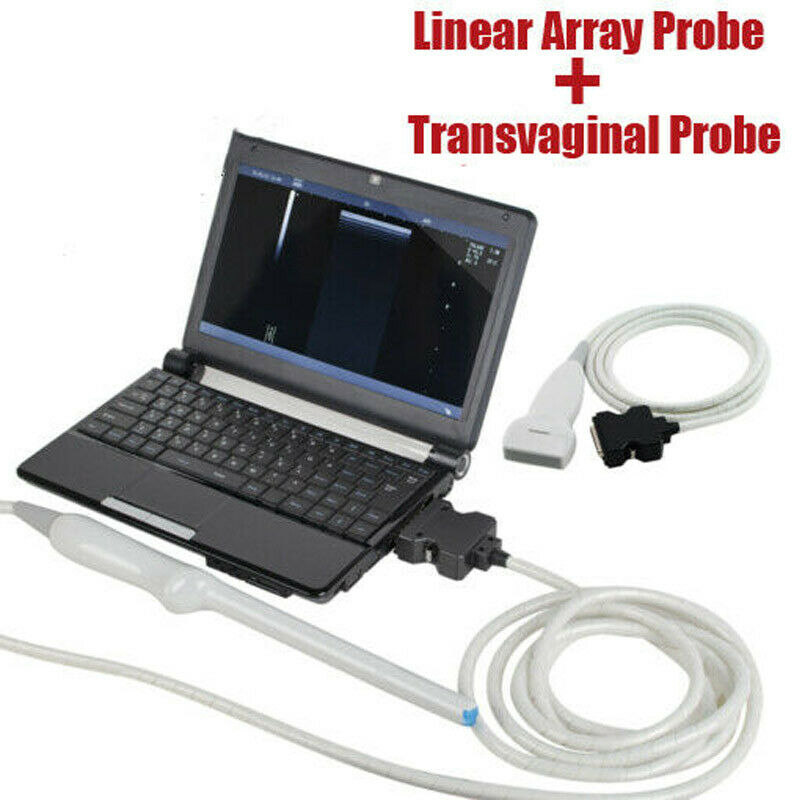

Pro Digital Laptop Ultrasound Machine Linear Array Probe + Transvaginal Probe

The Pro Digital Laptop Ultrasound Machine with a Linear Array Probe and Transvaginal Probe is a versatile and portable imaging system designed for a range of medical applications. This machine is suitable for both general diagnostics and specialized exams, including obstetrics and gynecology.

The included linear array probe provides high-resolution imaging, ideal for musculoskeletal, vascular, and soft tissue imaging. It delivers clear, detailed images for accurate diagnostics in various applications. The transvaginal probe is designed for internal imaging, offering clear visualization of the female reproductive organs, making it ideal for gynecological exams such as early pregnancy assessments and pelvic evaluations.

This laptop-style ultrasound machine is compact, lightweight, and portable, making it suitable for use in clinics, hospitals, or mobile medical units. It features an intuitive interface and customizable settings, streamlining the diagnostic process. This system combines advanced imaging capabilities with convenience and portability, making it an excellent choice for healthcare professionals.